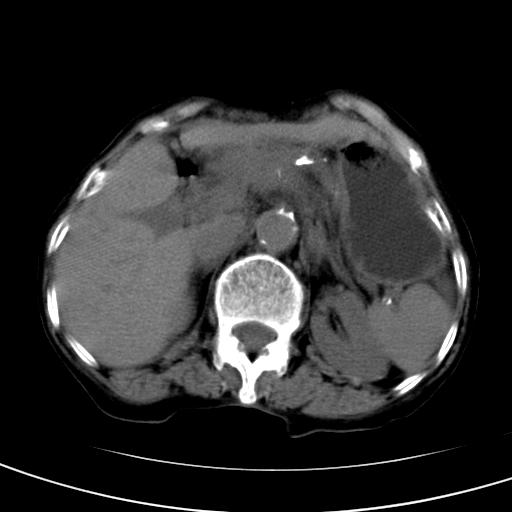

以下是引用wolft在2008-3-5 12:30:00的发言:[br]肝脏未见明显肿块影,但肝左叶增大,跨越腹中线到达脾胃前,且有一血管过去,考虑为先天变异:獭尾肝,胆囊为慢性胆囊炎急发,但胰腺头颈部有增大,密度不均匀,应该ct增强一下。

以下是引用zjzjr在2008-3-5 16:41:00的发言:[br]1.考虑慢性胰腺炎急性发作,建议增强除外占位性病变.[br]2.胆囊结石伴胆囊炎.[br]3.肝内胆管结石.